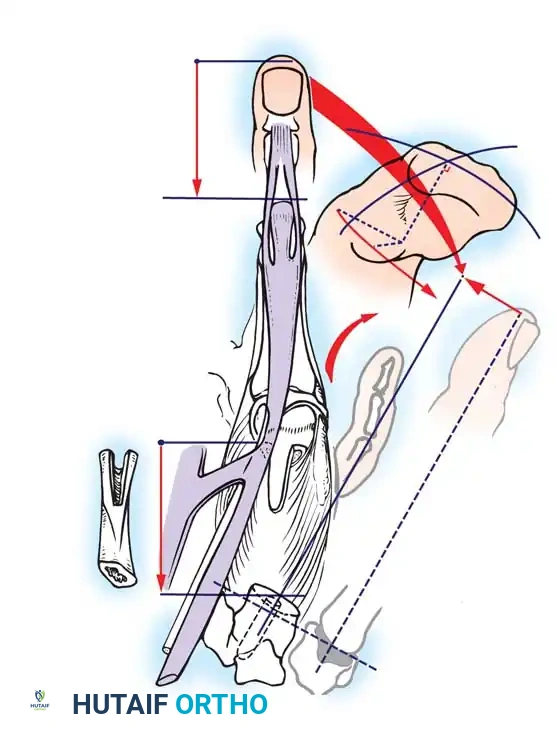

The Krukenberg procedure converts the forearm into a sensate pincer by separating the radius and ulna into two independent, opposing rays. Its primary advantage over prosthetic rehabilitation is the preservation of tactile sensibility and proprioception. This makes it an exceptionally valuable procedure for bilateral upper extremity amputees, particularly those who are blind, as it allows them to interact with their environment using direct sensory feedback.

- Incision and Flap Design: Make a longitudinal incision on the flexor surface of the forearm, biased slightly toward the radial side. Make a corresponding incision on the dorsal surface, biased toward the ulnar side. On the dorsal surface, elevate a V-shaped flap to form the new web space at the proximal junction of the rays.

- Muscle Separation: Systematically separate the forearm musculature into two distinct functional groups:

- Radial Ray (Adductors/Abductors): Comprises the radial wrist flexors and extensors, the radial half of the flexor digitorum sublimis (FDS), the radial half of the extensor digitorum communis (EDC), the brachioradialis, the palmaris longus, and the pronator teres.

- Ulnar Ray (Adductors/Abductors): Comprises the ulnar wrist flexors and extensors, the ulnar half of the FDS, and the ulnar half of the EDC.

- Debulking: If the muscle mass makes the stump too bulky or precludes tension-free skin closure, resect the pronator quadratus, flexor digitorum profundus (FDP), flexor pollicis longus (FPL), abductor pollicis longus (APL), and extensor pollicis brevis (EPB).

- Crucial Step: Take absolute care not to disturb the pronator teres, as it is the primary motor for the radial ray.

- Interosseous Membrane Division: Incise the interosseous membrane longitudinally along its ulnar attachment. Extreme caution must be exercised to preserve the anterior interosseous artery and nerve.

- Osteotomy and Alignment: The radial and ulnar rays should separate 6 to 12 cm at their tips. Motion occurs proximally at the radiohumeral and proximal radioulnar joints. The opposing distal ends of the rays must touch during active closure; if they do not, perform a corrective osteotomy of the radius or ulna.

- Skin Coverage: Excise excess subcutaneous fat. Rotate the skin around each ray and close it so that the suture lines do not lie on the opposing (contact) surfaces of the pincers. Apply split-thickness skin grafts to any remaining defects, ensuring the tactile contact surfaces are covered by sensate, full-thickness skin.

- Closure and Drainage: Suture the dorsal V-flap into the proximal junction to create the web. Insert small rubber drains, obtain meticulous hemostasis after tourniquet deflation, and apply a bulky compression dressing with the rays separated by at least 6 cm.